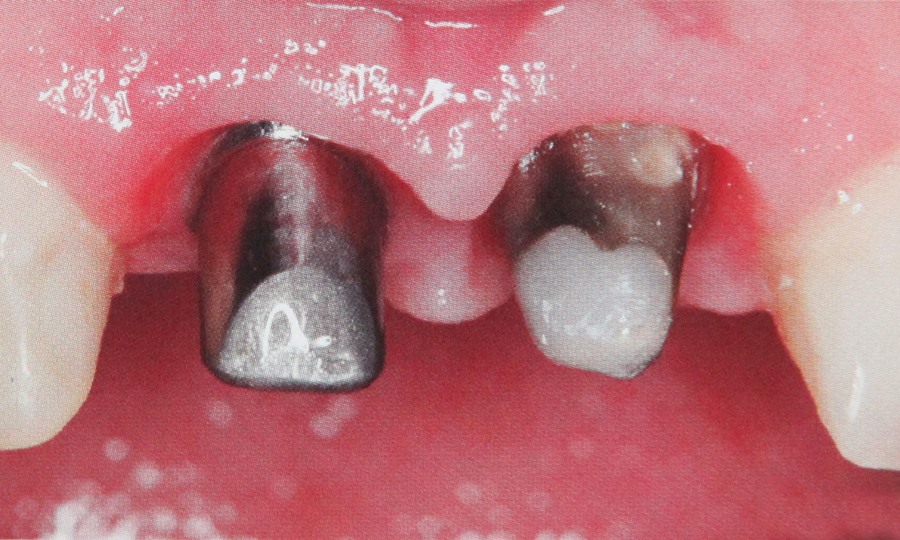

Presupune refacerea structurii dintelui utilizand lucrari protetice atunci cand caria dentara a afectat dintele intr-o masura prea mare pentru a putea fi remediat prin intermediul unei plombe. Daca dintele nu mai poate fi salvat si este extras spatiul lipsa poate fi completat fie printr-o lucrare protetica fie cu ajutorul unui implant. Daca pacientul pierde un numar mai mare de dinti se confectioneaza o proteza dentara.

Pentu ca folosim materiale de cea mai buna calitate pentru ca avem o colaborare stransa cu tehnicienii dentari si pentru ca acordam o atentie deosebita dorintelor pacientilor obtinem lucrari protetice care exceleaza prin estetica si functionalitate. Protetica inseamna refacere dentara prin lucrari protetice diverse.